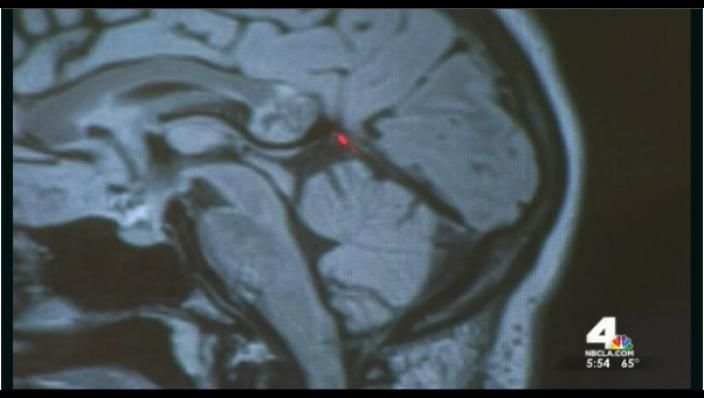

23 apr. 2015, 10:24LifestyleDescoperirea şocantă a chirurgului care a operat tumora pe creier a unei femei. Ce era, de fapt